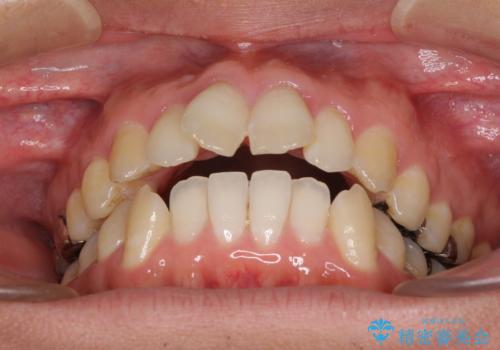

- 前歯のデコボコと、上顎前歯の突出感を気にして来院された患者様です。

通常の咬み合わせ位置と比較して、上顎の歯列が全体的に前方にある状態で、上下前歯の前後方向の位置に著しい差がありました。